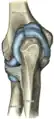

L'articulation du coude (ou articulation olécranienne) est la partie du membre supérieur située entre le bras et l'avant-bras. Cette articulation comprend en avant la région du « pli du coude » (ou fosse cubitale). C'est un complexe articulaire synovial du membre supérieur humain reliant le bras à l'avant-bras. Il unit ainsi trois os entre eux : le radius, l'ulna (cubitus) et l'humérus.

Elle est la réunion de trois articulations : huméro-ulnaire, huméro-radiale et radio-ulnaire proximale (supérieure). Lorsque l'avant-bras est tendu (extension complète), le bras et l'avant-bras ne sont pas alignés dans le plan frontal. Les deux parties forment un angle ouvert en dehors, d'environ 170° chez l'homme, 160° chez la femme ; c'est ce qui est appelé le valgus physiologique (on retrouve la même chose pour le genou).

Structures et surfaces articulaires

| Articulation | Entre | et | surfaces articulaires |

|---|---|---|---|

| Articulation huméro-ulnaire | Humérus | Ulna | Trochlée humérale / incisure trochléaire de l'ulna |

| Articulation huméro-radiale | Humérus | Radius | Capitulum de l'humérus / facette articulaire de la tête du radius |

| Articulation radio-ulnaire proximale | Radius | Ulna | Circonférence articulaire de la tête du radius et ligament annulaire du radius / incisure radiale de l'ulna |